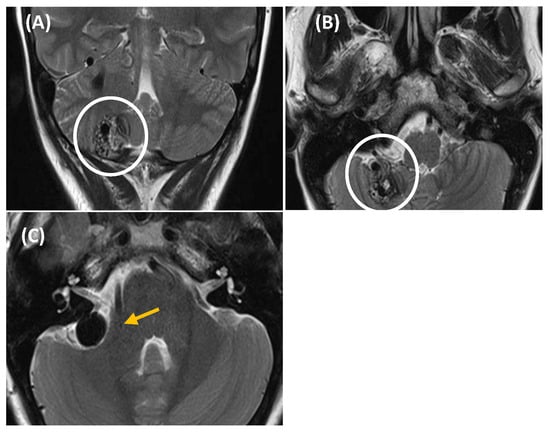

Figure 3. Aberrant intratympanic course of the right internal carotid artery, which is in contact with the cochlea (yellow arrow: aberrant ICA; blue arrow: cochlea). A 33-year-old man with right-sided PT of several years’ duration. Otoscopy revealed a pulsatile tumor in the right ear. CT imaging (A), axial plane bone window; (B), axial plane, contrast enhanced with soft tissue window; and (C), MPR coronal plane reconstruction) demonstrated a space-occupying lesion with a tubular appearance in the right mesotympanum, adjacent to the cochlear promontory, along with an enlarged inferior tympanic canaliculus and absence of the carotidotympanic bone septum.